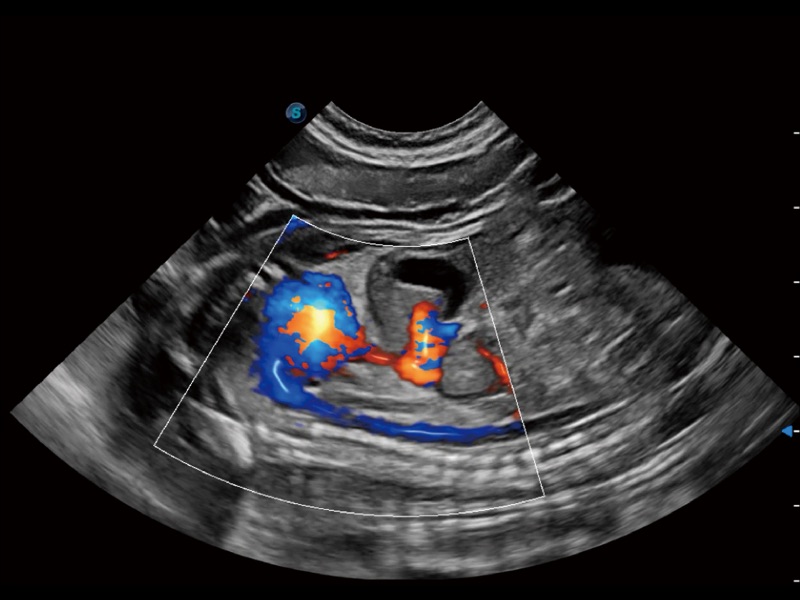

采用红、橙、黄、绿、青、蓝、紫这七种肉眼最为敏感的色彩,直观地显示组织内血流灌注的时间先后信息,更精准捕捉血流灌注走行细节。

能够基于左心室壁追踪和辛普森法,自动计算射血分数,支持多个可移动点描迹,与手动测量相比,极大节省了动物医生的时间和精力。

实时用颜色表示心肌组织运动,观察和定量组织的运动情况,对快速检测与评估心肌的灌注和活性、电传导及心肌收缩和舒张功能等均能提供重要的诊断信息。